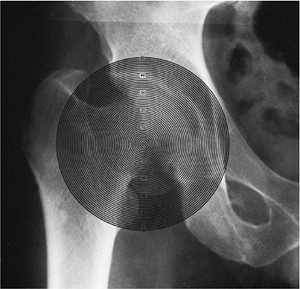

used a transparent protractor with concentric circles drawn at 2 mm of

radial difference to evaluate the shape of the femoral head. Mose

further developed Goff’s method and applied it clinically. This is the

most commonly used method of measuring sphericity (104,266,267,268) (Fig. 25.16).

superimposed on the AP and lateral radiograms. In the author’s

practice, if the outline of the femoral head is a perfect circle in

both projections, it is rated good; less than 2 mm of deviation is

rated fair; and more than 2 mm of deviation from a circle, in the AP or

lateral projection, is rated poor. Regardless of the measurements used,